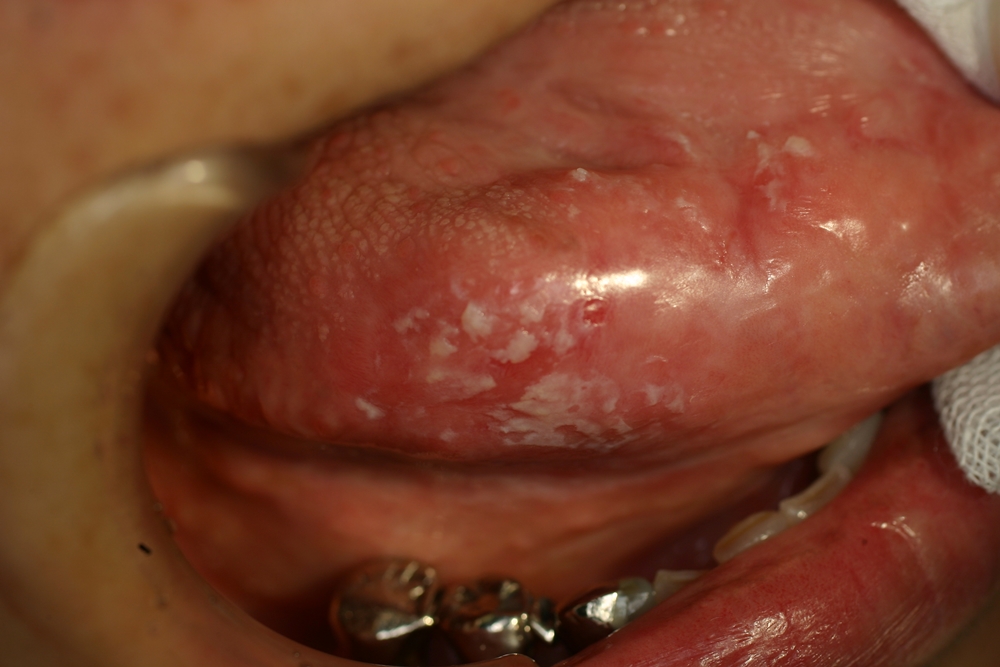

4.口腔カンジダ症

Candida albicansを主とする真菌(カビ)感染症で、口腔粘膜に白色病変として生じる白板症や扁平苔癬と異なり、白色の偽膜が擦過することで剥離出来ます。舌、頬粘膜に好発し、原因は唾液分泌低下、清掃不良、抗生物質による菌交代現象、全身状態の悪化などです。